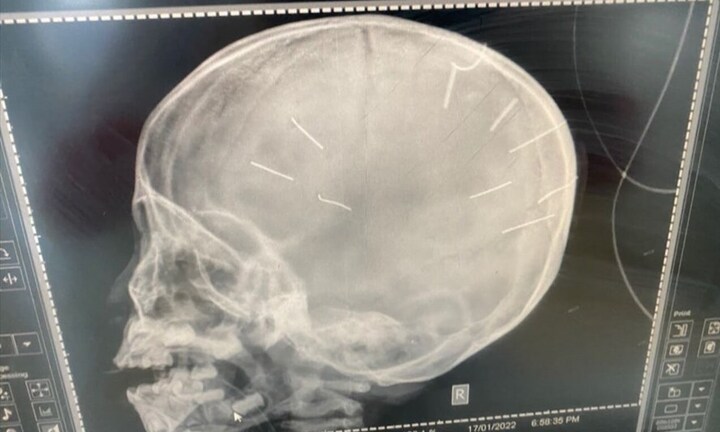

Nguyễn Trung Huyên được xác định là nghi phạm chính trong vụ việc bé gái 3 tuổi ở Canh Nậu (Thạch Thất, Hà Nội) bị cắm đinh vào đầu.

Theo khai nhận của bị cáo, khoảng 8h ngày 17/1, khi chị L. đi làm, Huyên tát vào mặt cháu A. nhiều lần. Thấy cháu khóc, hắn nhẫn tâm găm đinh vào xung quanh vùng đỉnh đầu của cháu bé.

Trước đó, nhiều lần Huyên cũng hành hạ cháu A. bằng các thủ đoạn khác nhau như cho uống thuốc trừ sâu, bắt nuốt đinh ốc vít, đánh gãy tay.